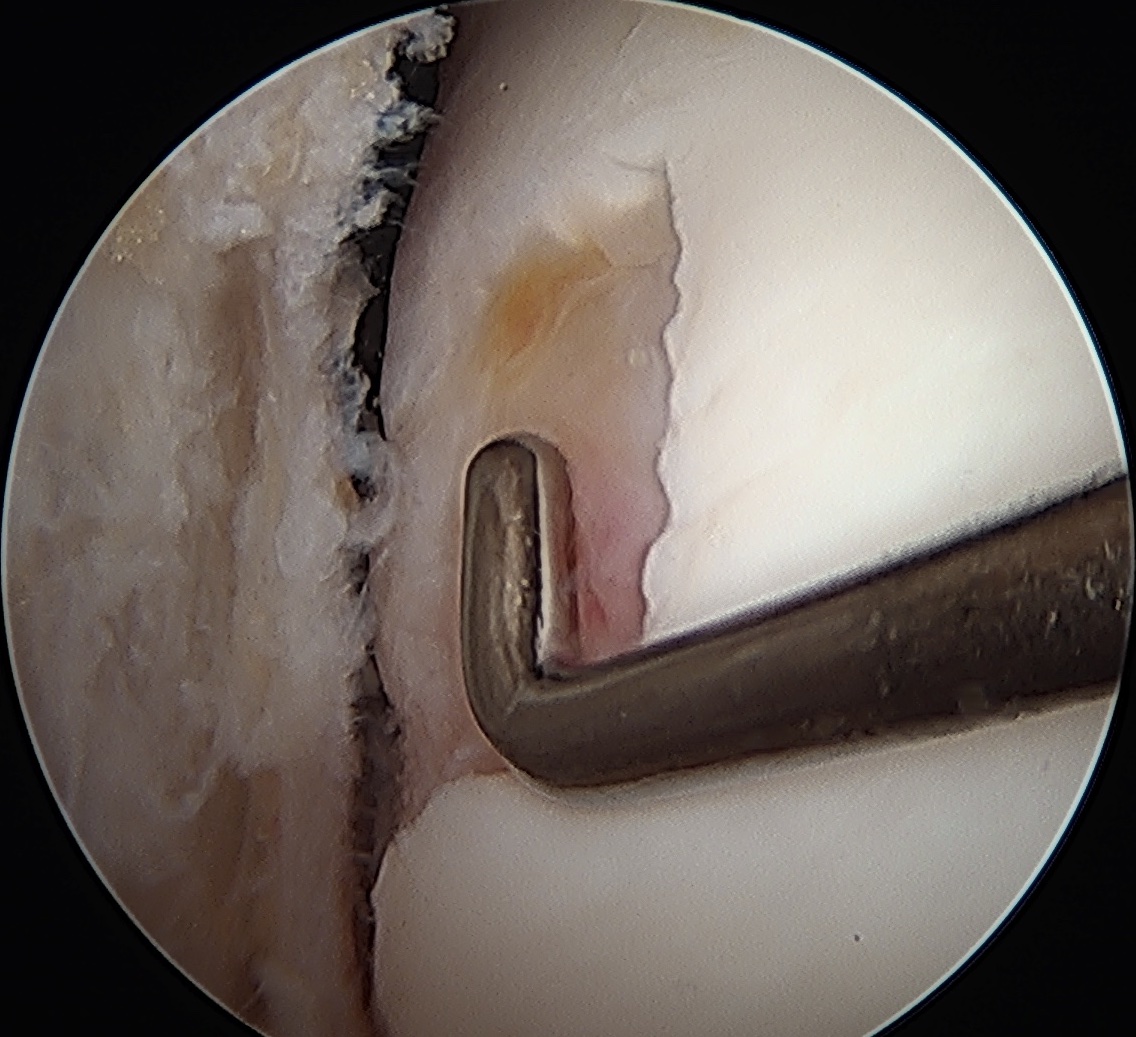

Sizing

3 or 5mm graduated probe

- measure in 2 dimensions

- give a size in cm2

- assumes that lesions are basically rectangular

- tend to overestimate size arthroscopically